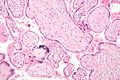

الصورة العليا: مشيمة بشرية بعد دقائق من الولادة. الجانب الظاهر في الصورة يواجه الجنين بالحبل السـُري أعلى اليمين. الطرف الأبيض المحيط بأسفل الصورة العليا هو بقايا الكيس السلوي amniotic sac. الصورة السفلى: مشيمة أخرى تـُظهر الجانب الذي يرتبط بجدار الرحم.